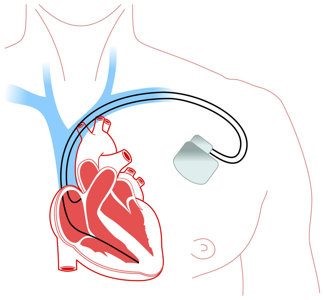

2. Двухкамерный: устанавливается в предсердии и желудочке сердца, что обеспечивает синхронное сокращение желудочков и предсердий, стимуляция становится физиологической, значительно увеличивая функциональные возможности пациента. В отличие от однокамерных стимуляторов, в данном случае происходят согласованные сокращения - предсердий вначале и только потом желудочков, обеспечивая правильный ток крови и полноценное заполнение кровеносных сосудов как при здоровом сердце.

Двухкамерный стимулятор отличается от однокамерного тем, что у однокамерного электрод стоит только в желудочке и стимулирует только желудочек сердца или только в предсердии, стимулируя только предсердие(всего одну камеру сердца, поэтому и называется однокамерным). Если электрод стимулирует желудочек, то предсердия сокращаются независимо. Это плохо тем, что иногда сокращения предсердий и желудочков могут совпадать, тогда кровь из предсердий пойдет не в желудочек, как ей положено, а обратно в вены. Это приведет к одышке, слабости. А у двухкамерного стимулятора один электрод стоит в предсердии, другой - в желудочке (то есть в двух камерах сердца) и координирует сердечные сокращения так, чтобы желудочки сокращались после предсердий, как и положено здоровому сердцу. Соответственно, двухкамерная стимуляция физиологичнее.

Операция является малотравматичной и относительно безопасной. Занимает от 40 минут до 2 часов (в зависимости от вида стимулятора). Операция проходит под местной анестезией: раствором новокаина или лидокаина обкалывают подключичную область (чаще слева). Делается разрез длиной до 5 см ниже ключицы. Под кожей формируется карман (ложе), в котором будет находится корпус стимулятора. Через подключичную вену электрод заводится в полость правого предсердия или желудочка при однокамерном, в полость правого предсердия и желудочка при двухкамерном стимуляторе. Существуют несколько видов электродов: